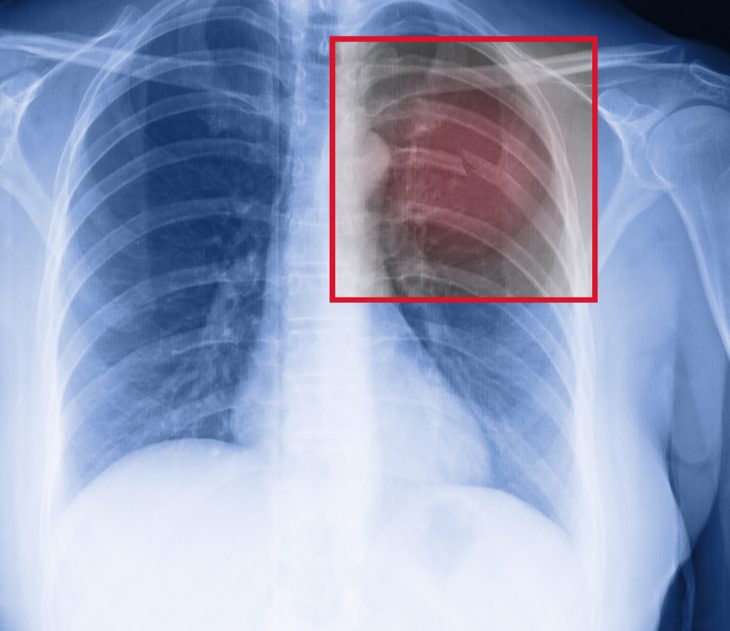

Для уточнения степени повреждения ребер и выявления скопления крови и других поражений могут назначаться такие дополнительные методы обследования:

- рентгеновские снимки (в переднезадней проекции);

- КТ;

- УЗИ грудной клетки.